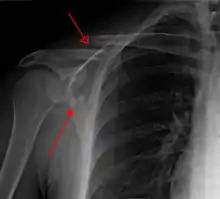

Most fractures of the scapula can be seen on a chest X-ray; however, they may be missed during examination of the film.[1] Serious associated injuries may distract from the scapular injury,[4] and diagnosis is often delayed.[3] Computed tomography may also be used.[1] Scapular fractures can be detected in the standard chest and shoulder radiographs that are given to patients who have suffered significant physical trauma, but much of the scapula is hidden by the ribs on standard chest X-rays.[4] Therefore, if scapular injury is suspected, more specific images of the scapular area can be taken.[4]